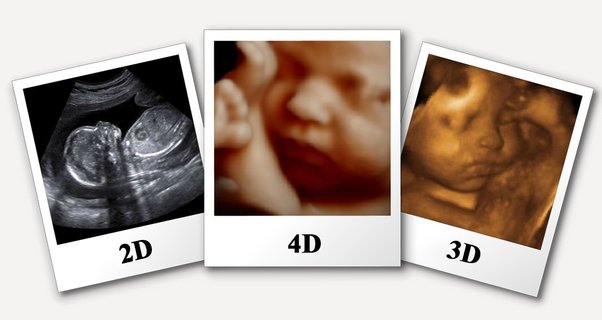

Siêu âm 4D là một kỹ thuật siêu âm hiện đại sử dụng sóng âm để tạo ra hình ảnh chuyển động 3D hoặc 4D của thai nhi. Kỹ thuật này có nhiều lợi thế vượt trội so với siêu âm 2D và 3D, mang đến cho mẹ bầu những trải nghiệm thú vị khi nhìn thấy con yêu một cách rõ nét và chân thực.

Kỹ thuật này giúp mẹ bầu có thể nhìn thấy rõ hơn hình dáng, chuyển động và các đặc điểm của thai nhi trong 3 chiều không gian và 1 chiều thời gian.

Tương tự như siêu âm thai 2D, 3D, siêu âm 4D cũng có thể giúp xác định tuổi thai, vị trí nhau thai, theo dõi sự phát triển của thai nhi,... Bên cạnh đó, siêu âm 4D còn có những lợi thế sau: